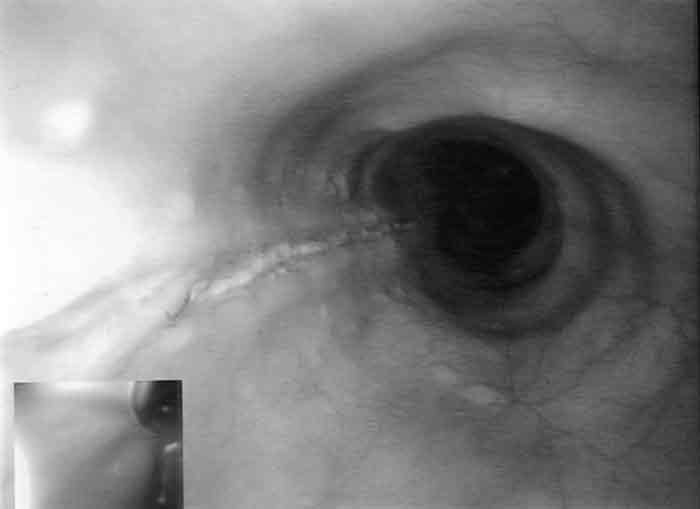

The patient was admitted and managed with nil by mouth, intravenous fluids, triple intravenous antibiotic therapy (ampicillin 1 g four times a day, gentamicin 5 mg/kg daily [with subsequent doses titrated according to drug level], metronidazole 500 mg twice a day), intravenous omeprazole 40 mg three times a day, and frequent observation. Her fever resolved within 24 hours, but her C-reactive protein level rose to 18.2 mg/L (reference range, 0–8.0 mg/L). A second CT scan, with water-soluble contrast, showed intramural contrast with no extravasation, consistent with a partial perforation of the oesophagus (Box 1). Gastroscopy revealed a 10 cm longitudinal mucosal/submucosal tear in the left posterolateral wall of the oesophagus 3 cm above the gastro-oesophageal junction (Box 2A), and a small sliding hiatus hernia. The rest of the oesophagus, stomach and duodenum were normal.

The patient’s symptoms improved with conservative treatment. She started clear fluids on Day 4, progressed to a soft diet, and was discharged on Day 7 with a prescription for oral omeprazole 40 mg daily. After 4 weeks, she still had occasional mild discomfort on swallowing. A repeat gastroscopy showed the healed scar of the tear, with no evidence of stricturing (Box 2B). Gastroscopy also revealed uncoordinated peristalsis of the oesophagus, but video fluoroscopy excluded dysmotility.